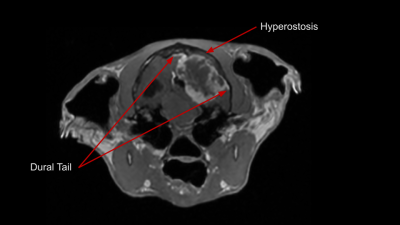

Mengiomas are typically benign and slow growing tumors arising from the meninges. They can occur anywhere along the CNS, but are most common around the brain. Meningiomas have a few key identifying characteristics:

- Vivid contrast enhancement

- 'Dural Tail' sign

- Compression or herniation of other brain structures

- Hyperostosis (bony overgrowth) of the cranium by the tumor